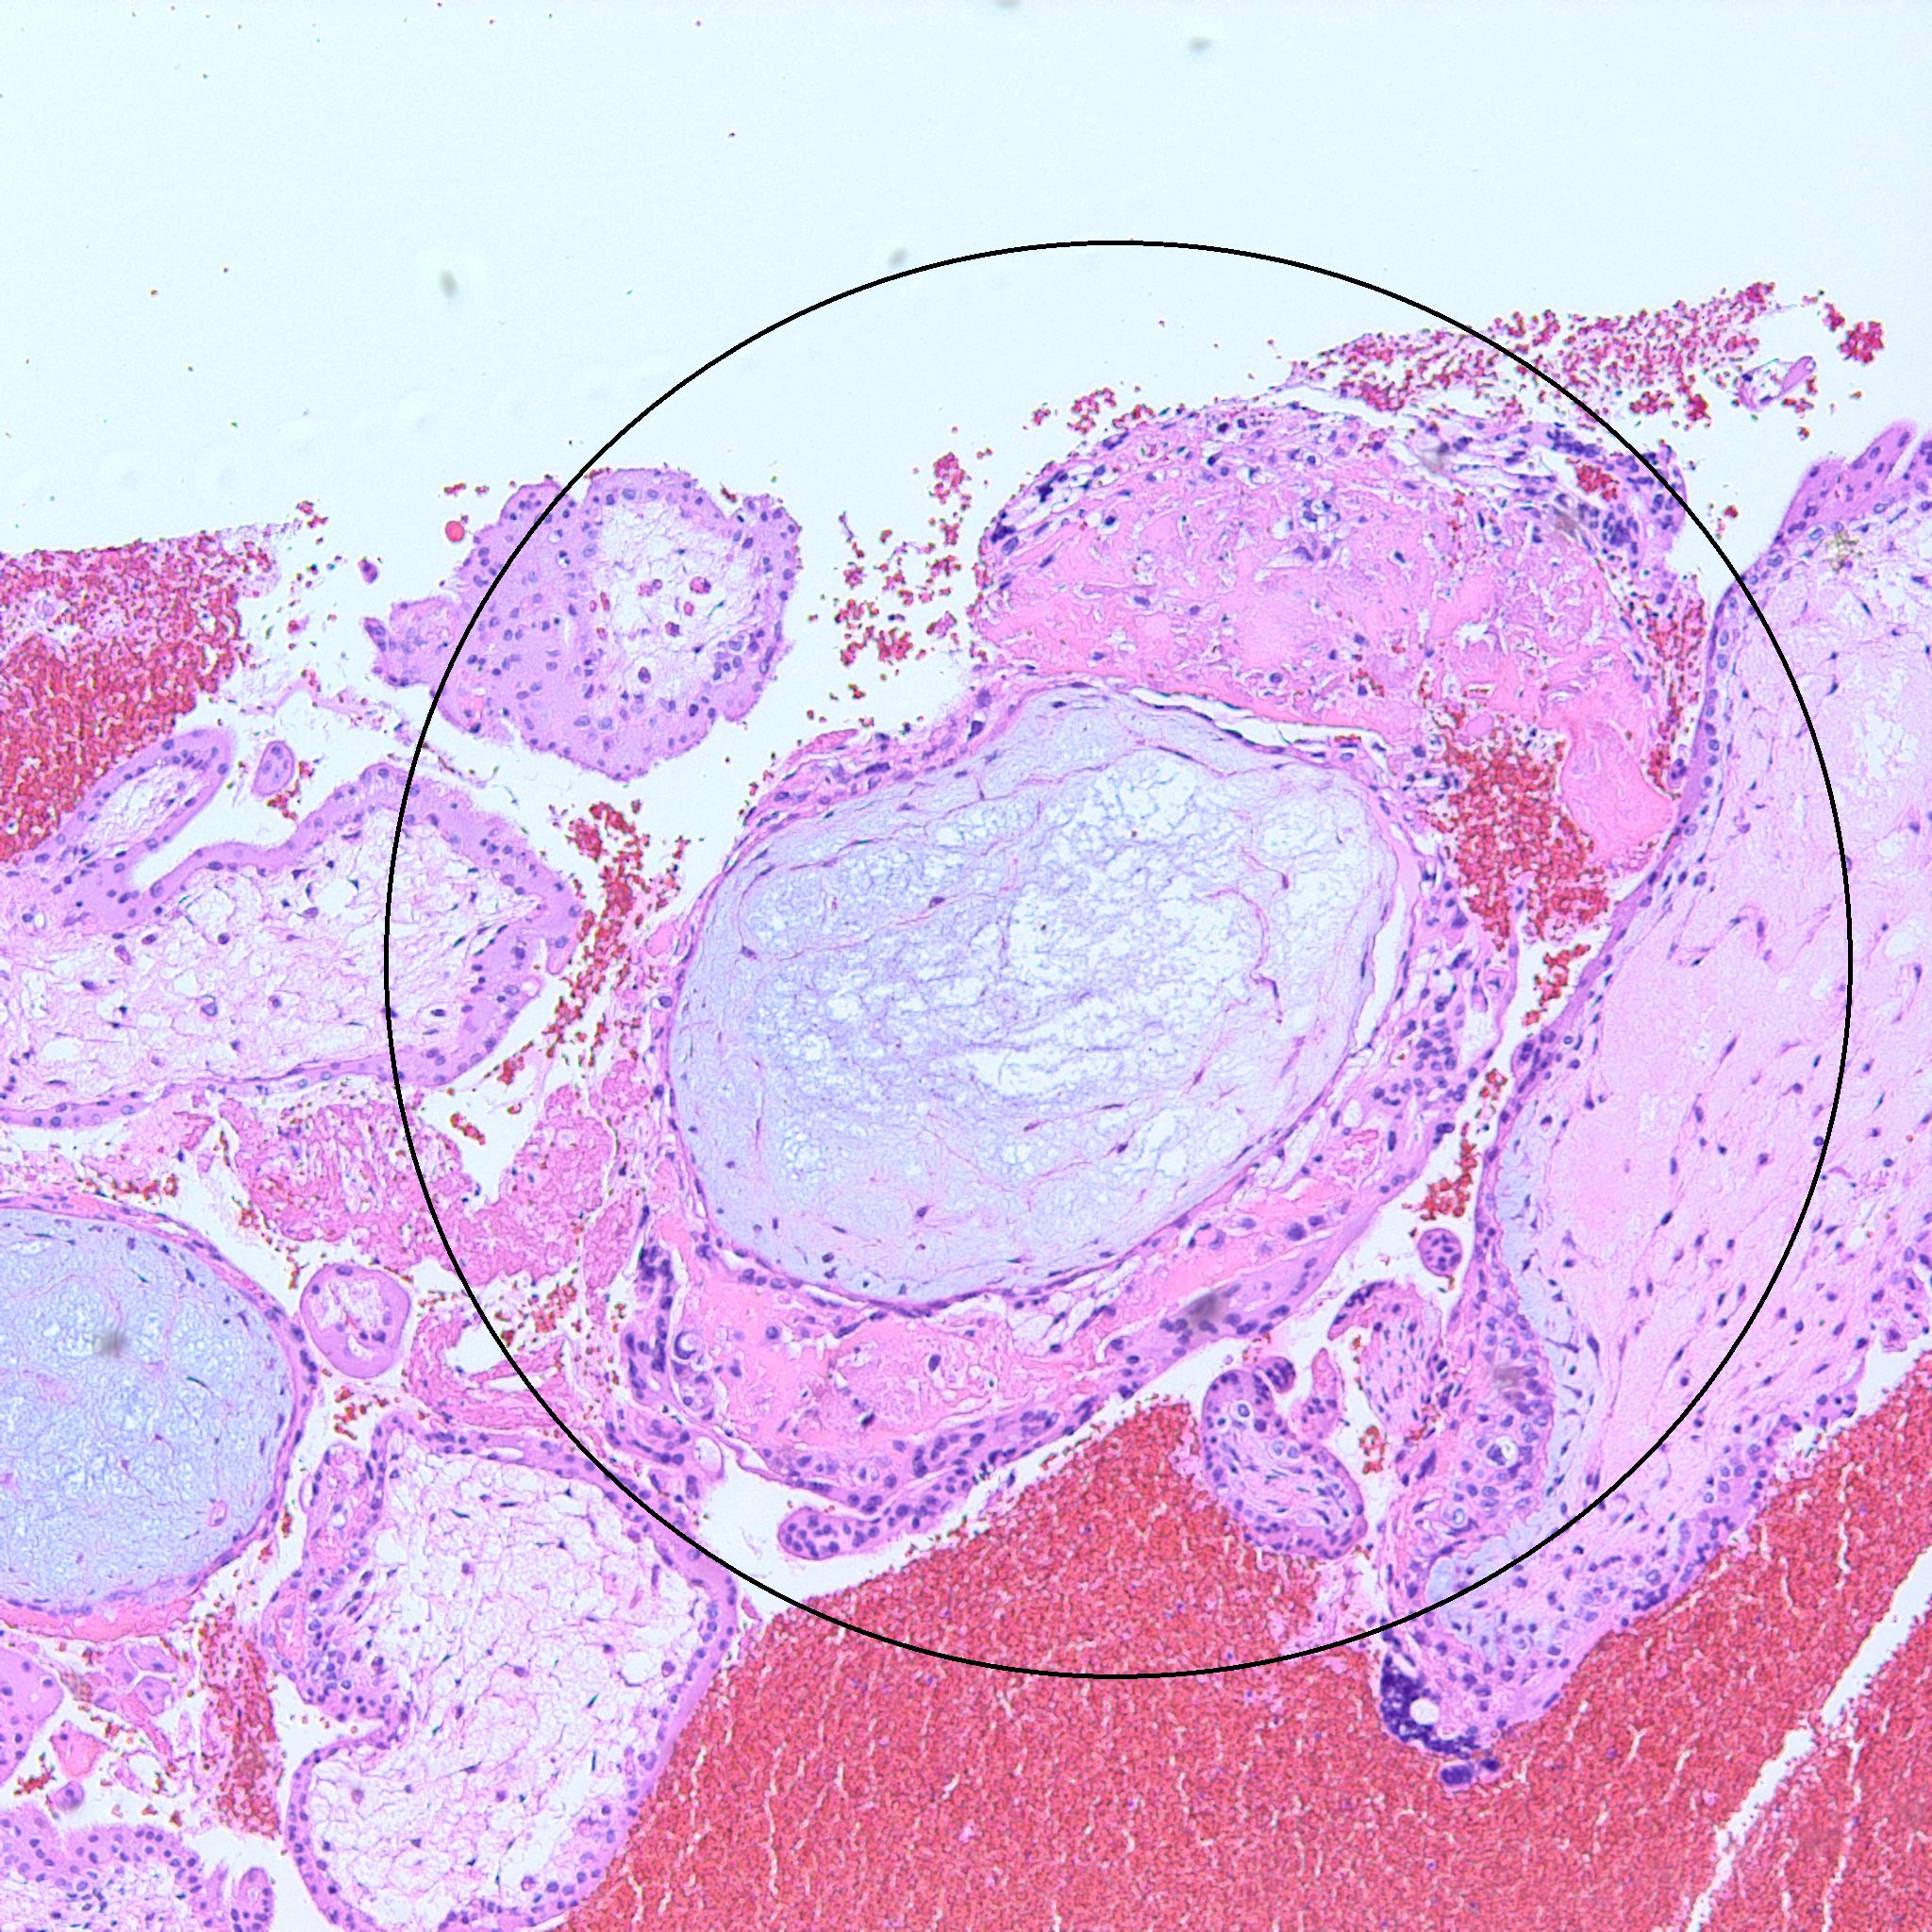

At low power we see throughout the specimen that numerous enlarged hydropic chorionic villi are present (circles).

As we can see, enlarged and hydropic chorionic villi are not especially difficult to find (circle). None of these villi however demonstrate trophoblastic inclusions. There are rare interspersed small chorionic villi (top left) however they are generally rare.

Some villi are so large and hydropic that a few have actually developed central cisterns, spaces within the center of the villi (space highlighted by horizontal lines).

This large hydropic villus with central cistern also demonstrates an important finding: the loss of polarity of the surrounding trophoblasts with circumferential proliferation of variably atypical trophoblastic cells (arrows).